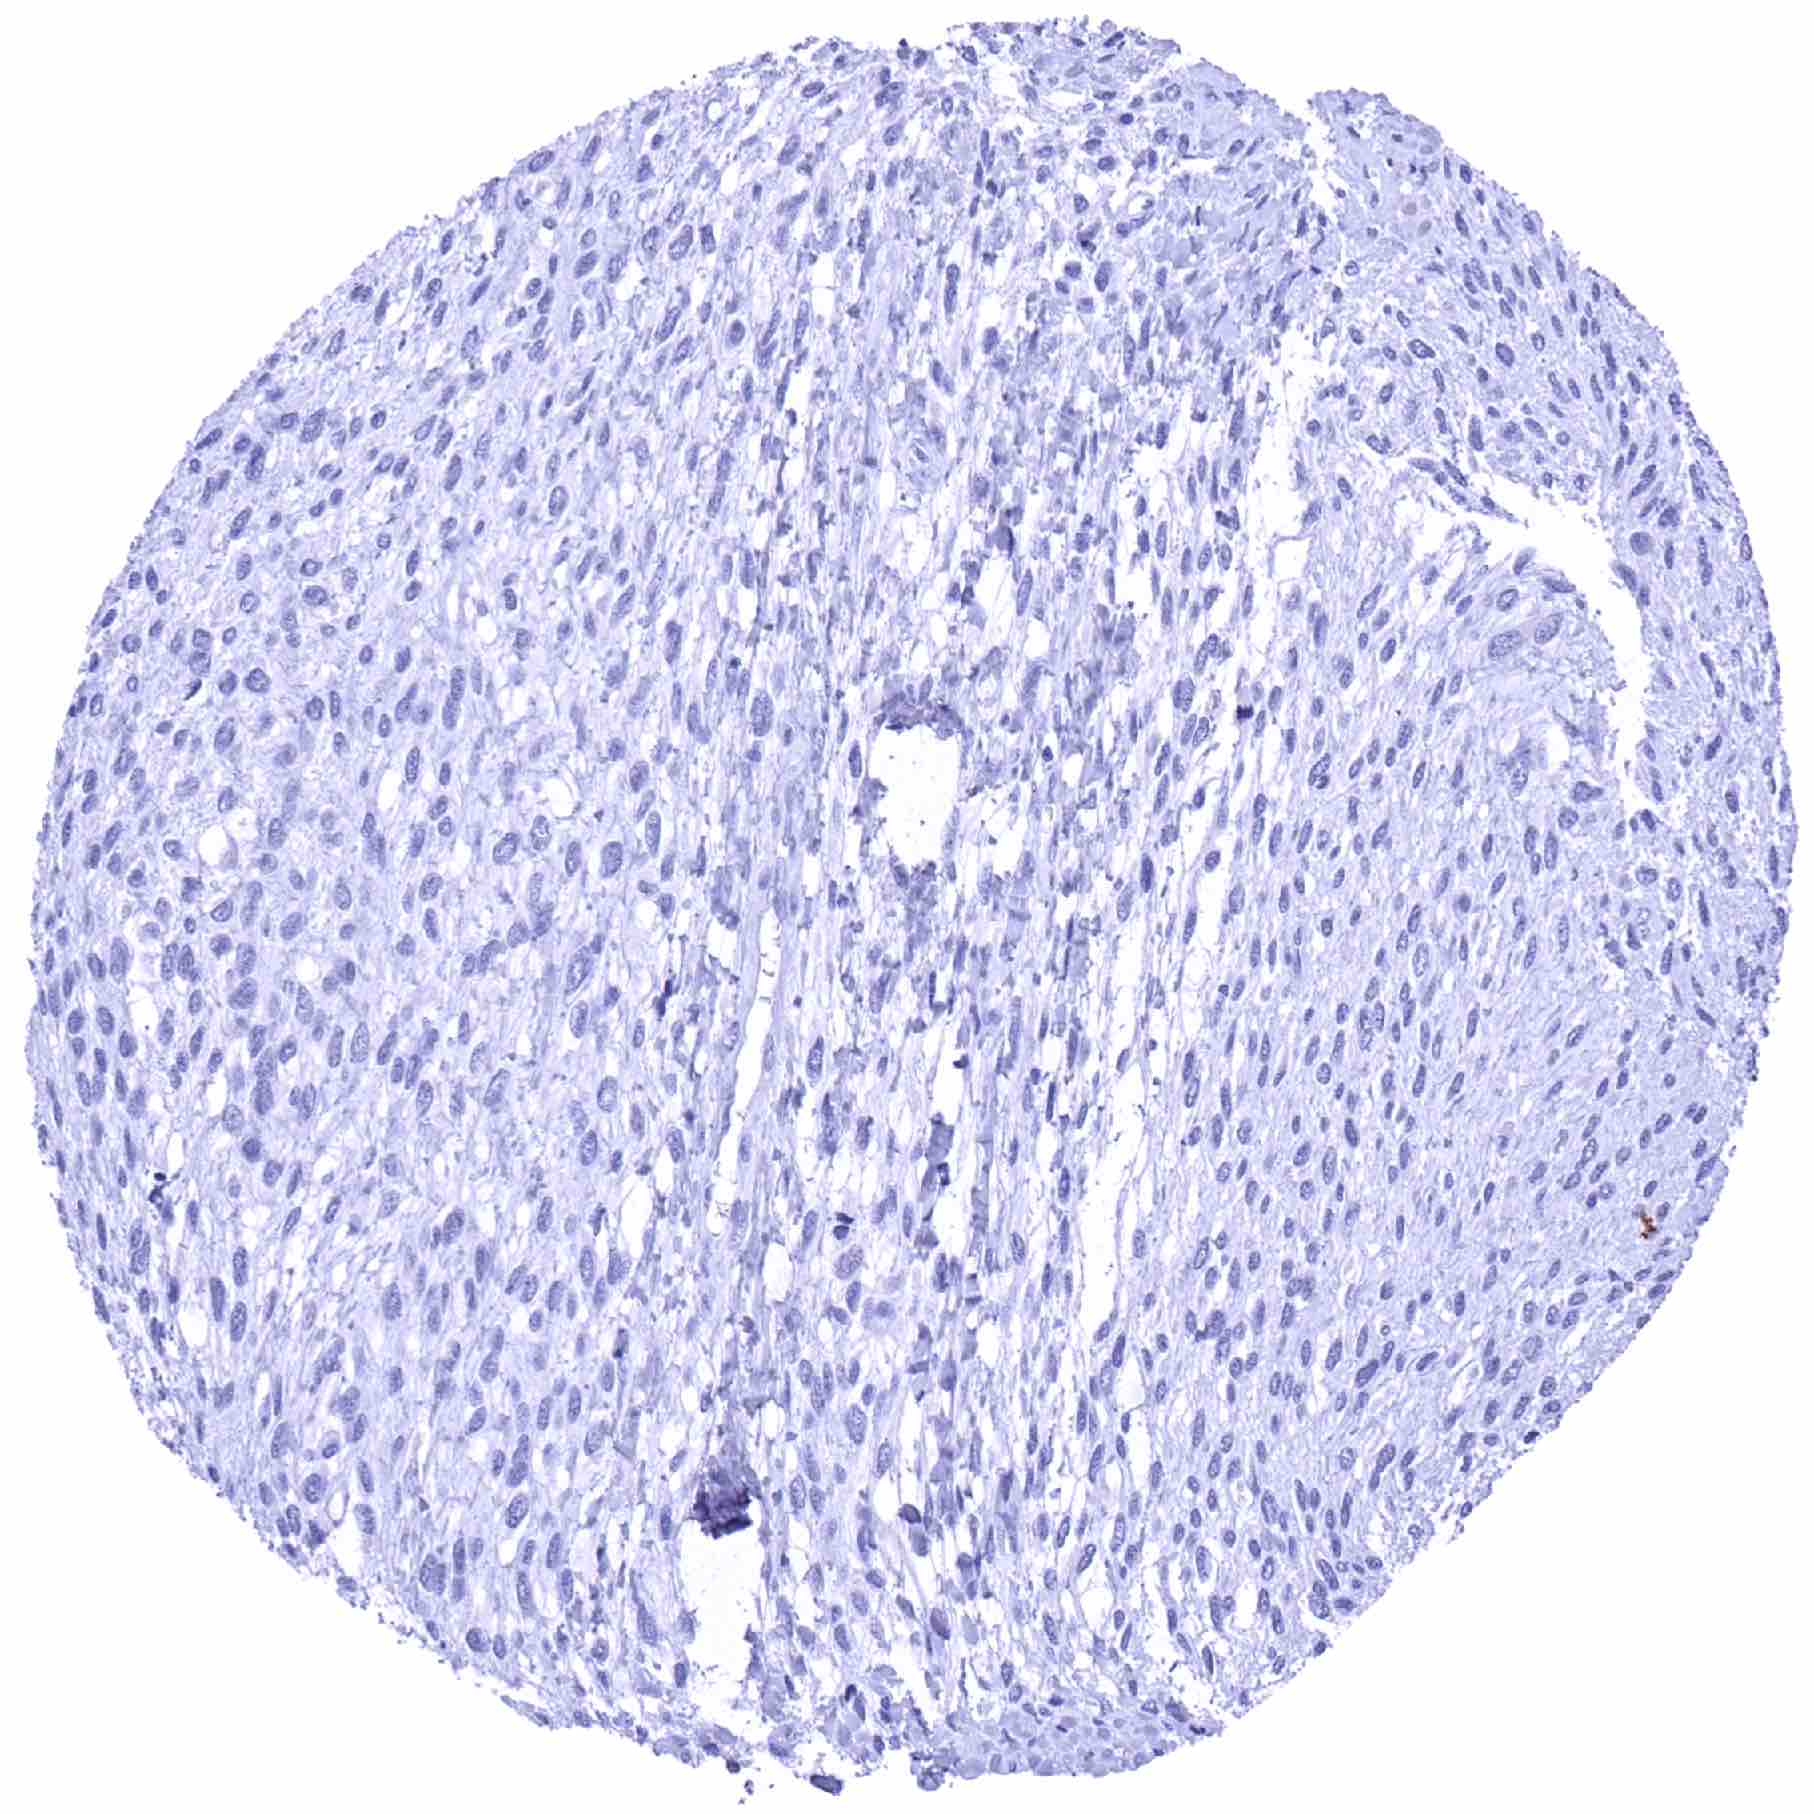

Breast – TRIM72 negative invasive breast cancer of no special type (NST)